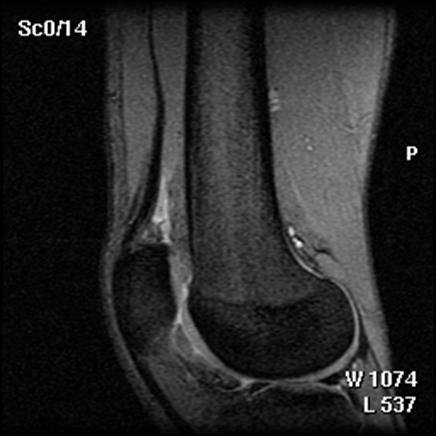

1. Imaginile RMN

Din 48 de pacienti tratati cu tehnica de microfracturare in studiul nostru , 24 (50%) au acceptat sa fie evaluati prin imagini ale rezonantei magnetice. RMN a fost facuta doar pentru studiu si nu datorita vreunui simptom clinic si s-a efectuat in medie la 12 2 luni (de la 3 la 36 de luni) dupa operatie. Imaginile au fost executate la mai putin de 6 luni pentru 3 pacienti (13%), de la 6 la 12 luni pentru 15 pacienti (61%) si mai mult de 12 luni dupa microfracturi pentru 6 pacienti (26%). Sase pacienti au o serie de imagini RMN cu media 1,3 0,1 (de la 1 la 3 scanari) pe pacient. La acesti 6 pacienti, descoperirile la cea mai recenta evaluare imagistica au fost folosite pentru analiza rezultatelor functionale. Nu s-au gasit diferente semnificative intre pacientii cu sau fara evaluare imagistica RMN cu privire la datele demografice (p> 0,650); caracteristicile leziunilor (p>0,450); durata preoperatorie a simptomelor (p= 0,793); indexul masei corporale (p= 0,217); durata urmarii postoperatorii (p= 0,902); si scorul preoperator si postoperator pentru activitatile zilnice(p=0,250); SF-36componenta fizica (p= 0,250), IKDC (p= 0,820) si rata subiectiva (p = 0,867).

Fig.32. Imagine RMN pacient T.C. 19 ani

Fig.33. Imagine RMN T.C. 19 ani

Fig.34. A-scanare inaintea microfracturarii, B-scanare la patru luni dupaa microfracturare.

Evaluarea imaginilor RMN a fost realizata de catre radiologist cu experienta, care cunostea situatia pacientilor si operatia efectuata. Imaginile au fost astfel analizate incat sa se observe zonele cu cartilaj de reparare comparativ cu cel nativ. Repararea morfologica a fost descrisa ca depresiva, neteda, sau mareata comparativ cu cartilajul nativ inconjurator. Volumul de umplere al defectului cu cartilaj reparator a fost masurat folosind imagini sagitale si coronale si a fost gradat ca bun (intre 67% si 100%), moderat (34% la 66%), sau slab (0% la 33%) pe baza procentajului defectului umplut. Interfata cu suprafata cartilajului nativ adiacent a fost evaluata si gradata ca fiind mica ( gaura ≤ 2mm) sau mare (gaura ˃ 2mm). Edemul maduvei osului subcondral a fost gradat ca fiind usor (˂ 1 cm²), moderat (intre 1 si 3 cm²) sau sever (˃ 3 cm²), iar prezenta sau absenta cresterii osoase a fost atent inregistrata.